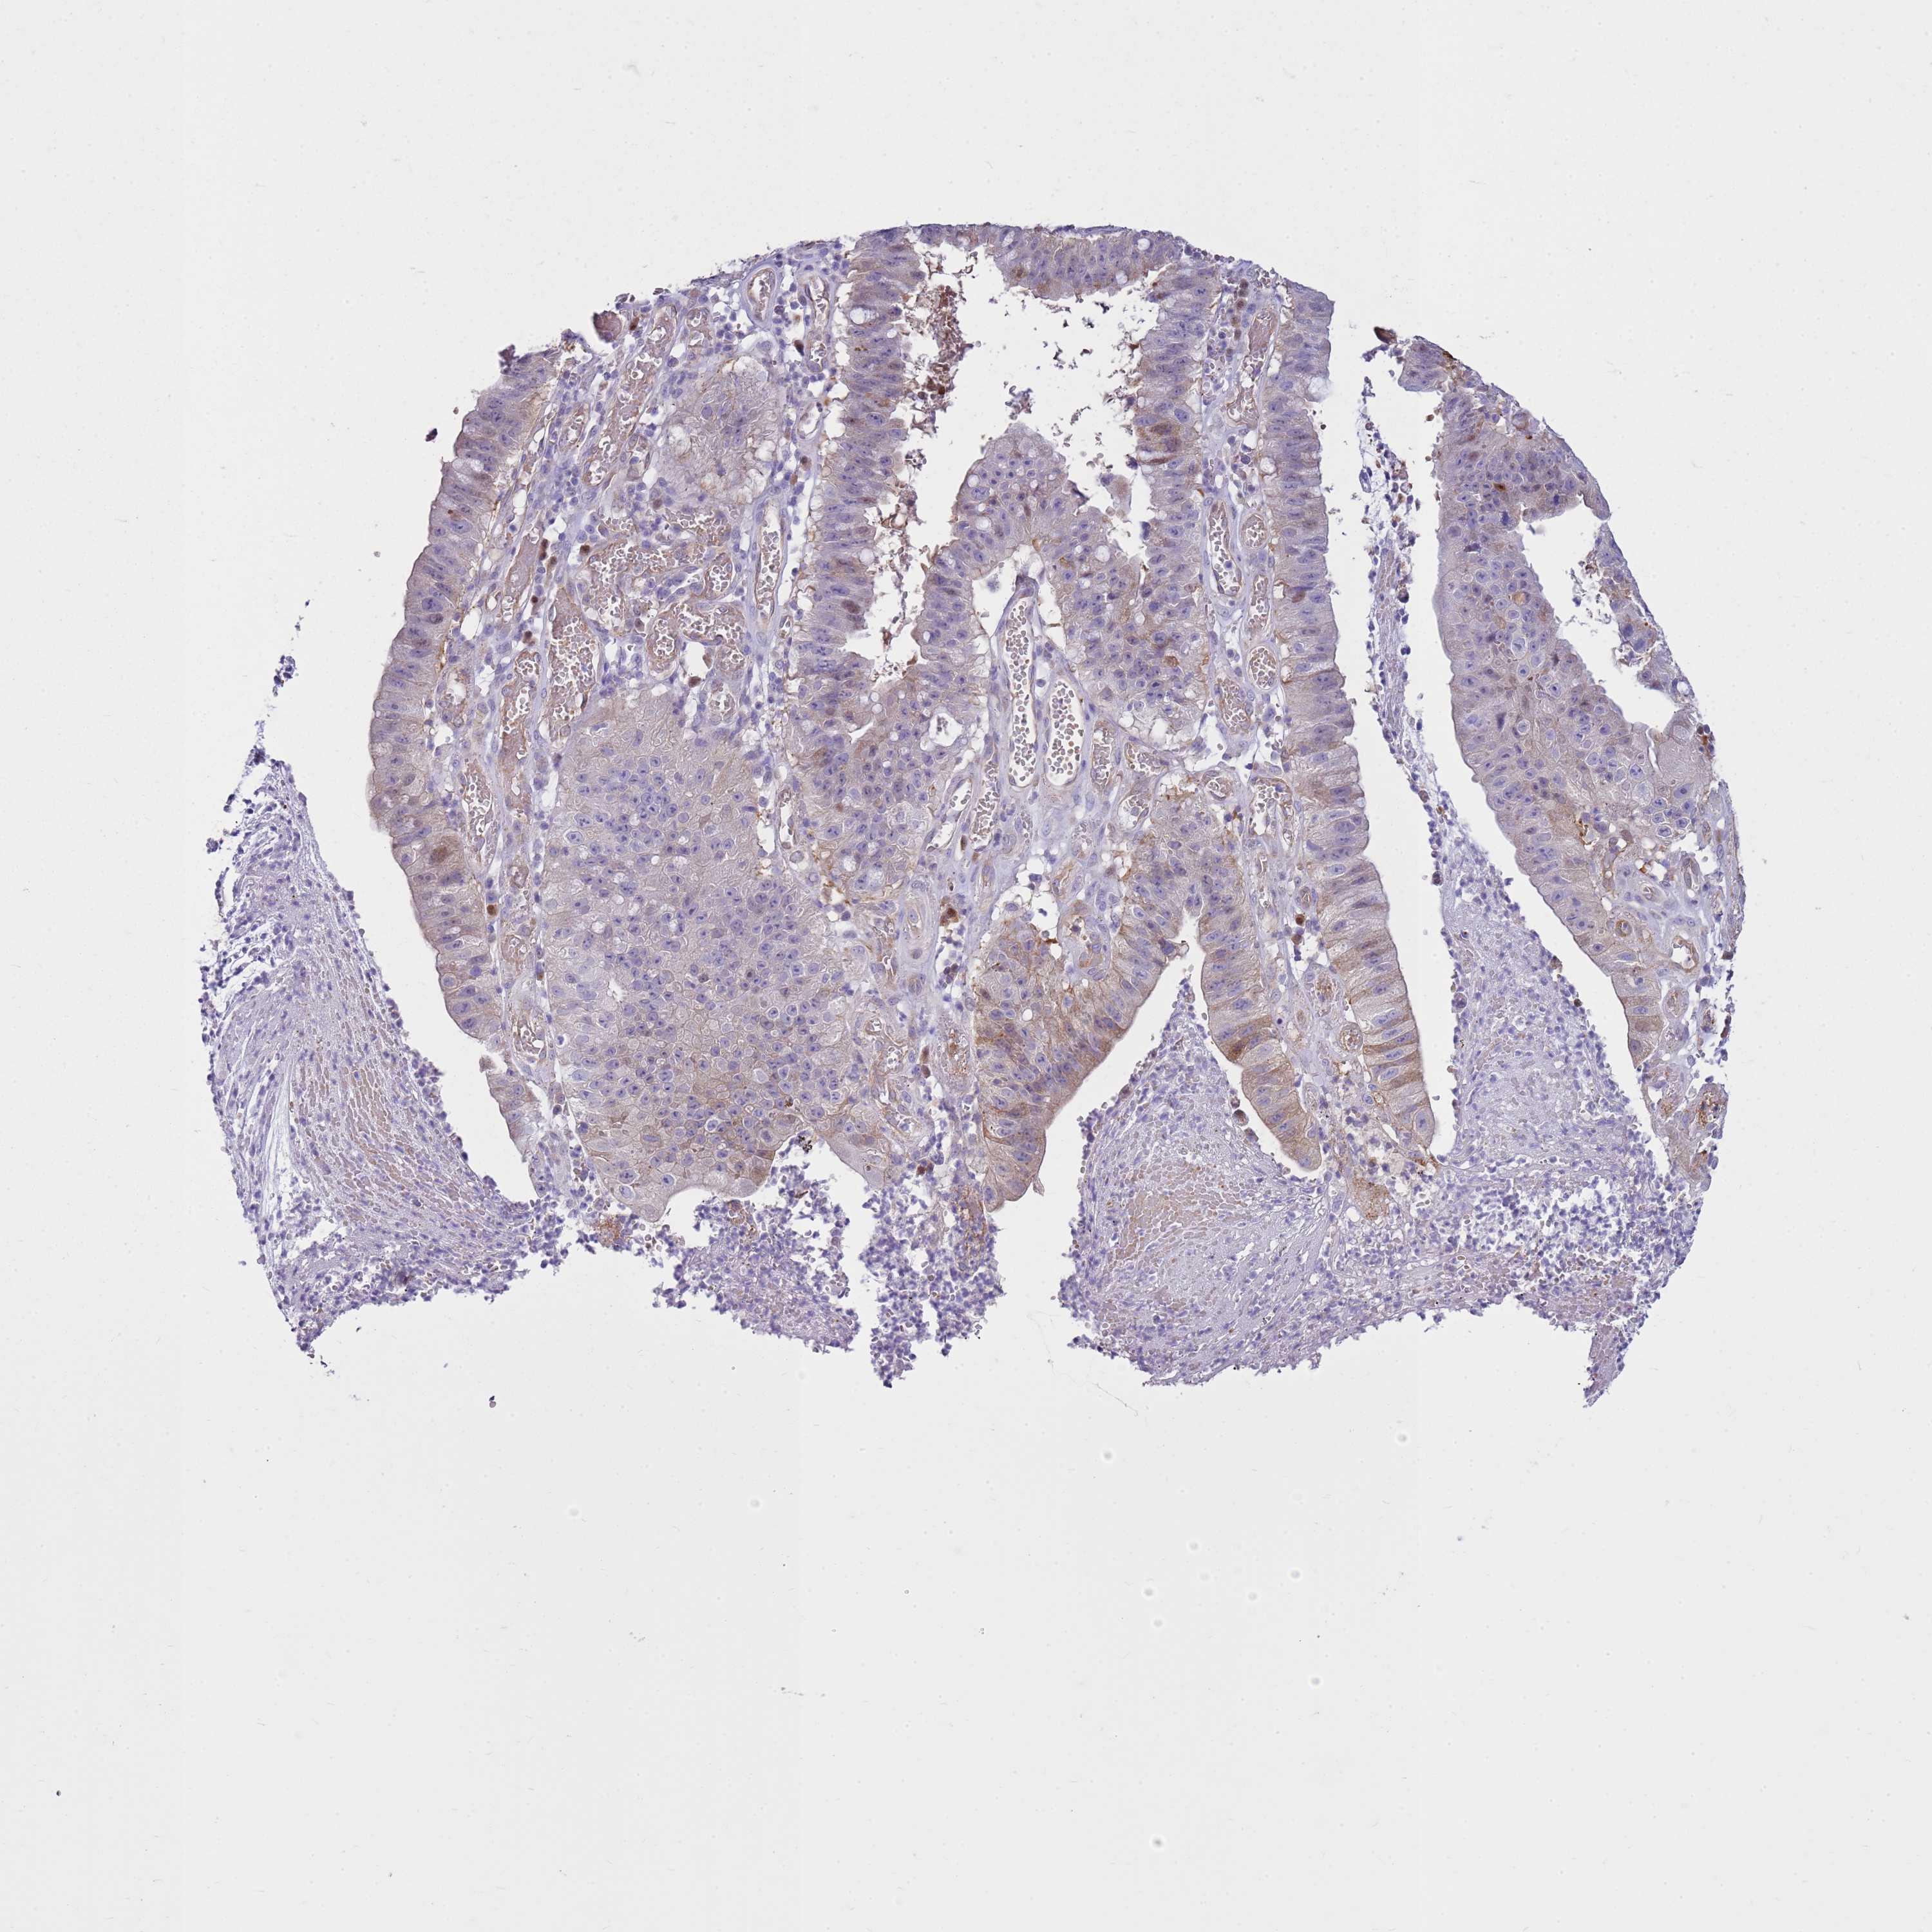

STOMACH CANCER - Protein expressioni

A mouse-over function shows sample information and annotation data. Click on an image to view it in a full screen mode. Samples can be filtered based on level of antibody staining by selecting one or several of the following categories: high, medium, low and not detected. The assay and annotation is described here.

Note that samples used for immunohistochemistry by the Human Protein Atlas do not correspond to samples in the TCGA dataset.

Antibody stainingi

Antibody staining in the annotated cell types in the current human tissue is reported as not detected, low, medium, or high, based on conventional immunohistochemistry profiling in selected tissues. This score is based on the combination of the staining intensity and fraction of stained cells.

Each image is clickable and will lead to virtual microscopy that enables deeper exploration of all samples and also displays staining intensity scores, fraction scores and subcellular localization as well as patient and tissue information for each sample.

Antibody HPA008445

Antibody CAB016200

Antibody CAB021109

Antibody CAB047350

Staining

High

Medium

Low

Not detected

Intensity

Strong

Moderate

Weak

Negative

Quantity

>75%

75%-25%

<25%

None

Location

Nuclear

Cytoplasmic/membranous

Cytoplasmic/membranous,nuclear

Adenocarcinoma, NOS

Adenocarcinoma, High grade